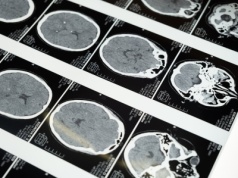

Nowe badanie pokazuje, że połączenie dwóch terapii epigenetycznych może skuteczniej hamować rozwój śmiertelnych guzów mózgu u dzieci. Artykuł Nowe badanie: podwójna terapia daje nadzieję na leczenie raka mózgu u dzieci pochodzi z serwisu Alert Medycz...